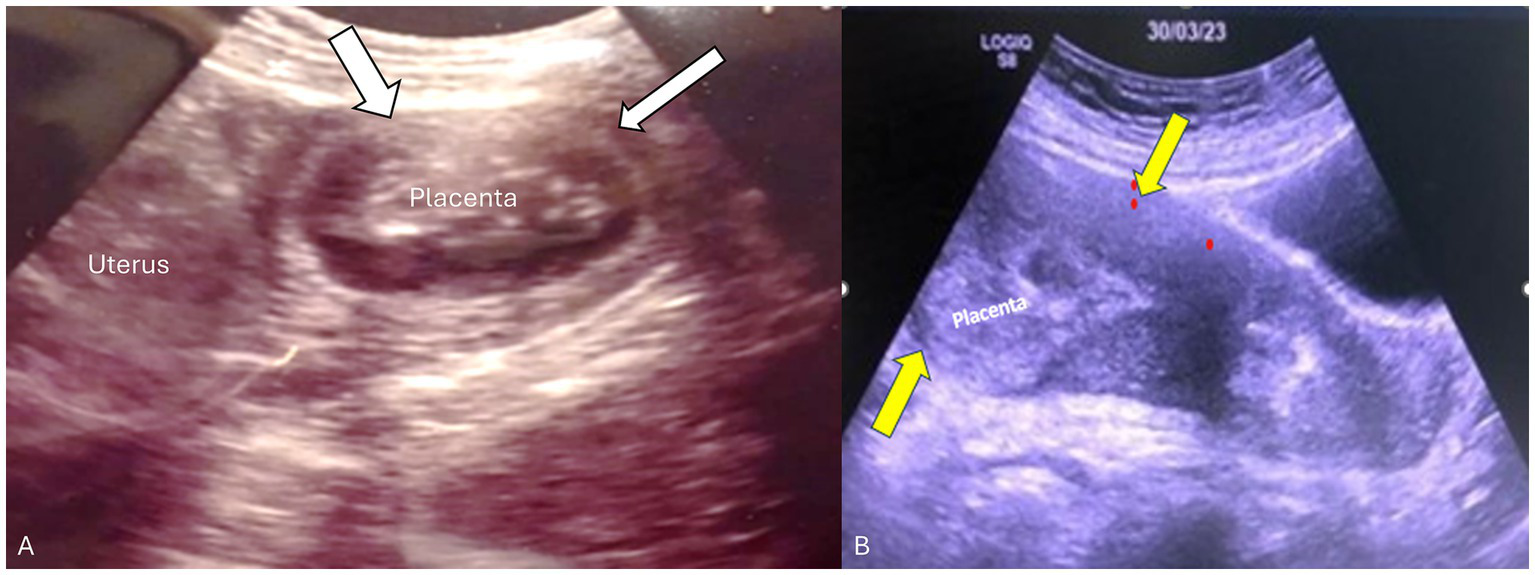

Figure 1

Transabdominal ultrasound of the placenta and uterus in both patients. (A) Transverse view of the uterus showing the placenta in the left cornua 14 weeks postpartum. Myometrial thinning was seen in the fundal portion adjacent to the placenta consistent with placenta accreta/adherent (white arrows). (B) Sagittal view of the uterus showing retained fundal placenta. Yellow arrows demonstrate a thick contracted anterior-wall myometrium whereas the posterior uterine wall is very thin (non-detached partial placenta adherent).